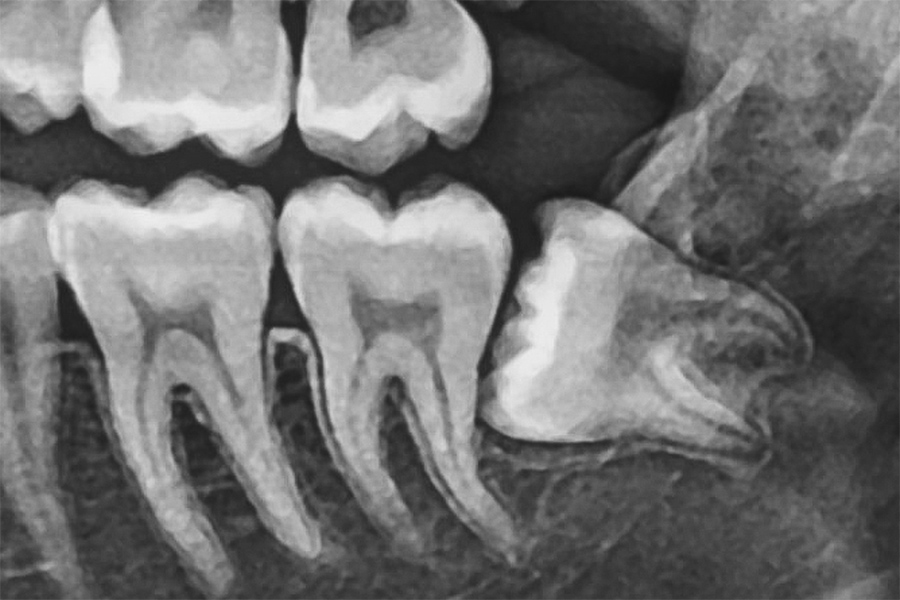

「水平埋伏歯」にも対応

水平埋伏歯」とは、横向きに生えている歯のことです。この歯は手前の歯を圧迫し、痛みや歯並びの乱れを引き起こす可能性があります。また、虫歯歯周病の原因にもなります。

このような歯は骨や神経に非常に近い位置にあるため、抜歯には高い技術が求められます。当院では、精密な診断と高度な技術により、難しい抜歯にも対応しています。他院で断られたケースでも、まずはご相談ください。